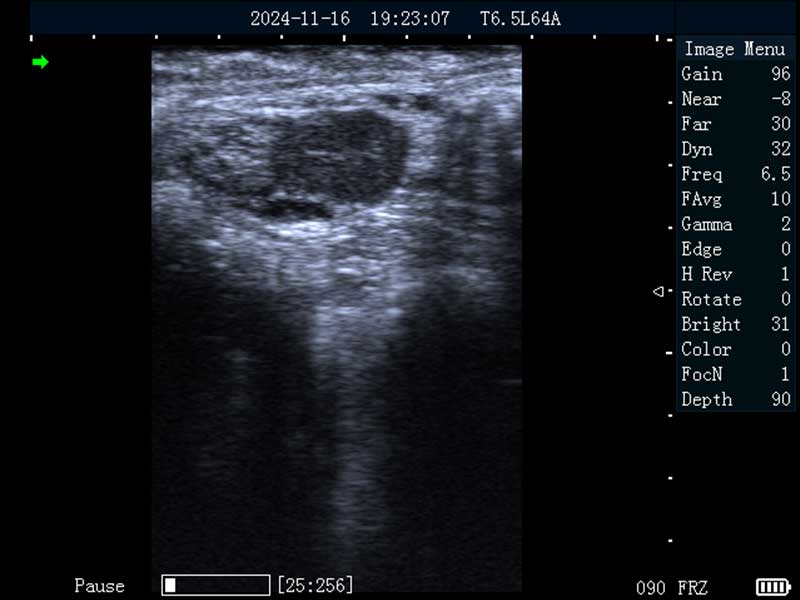

牛黄体

牛卵巢